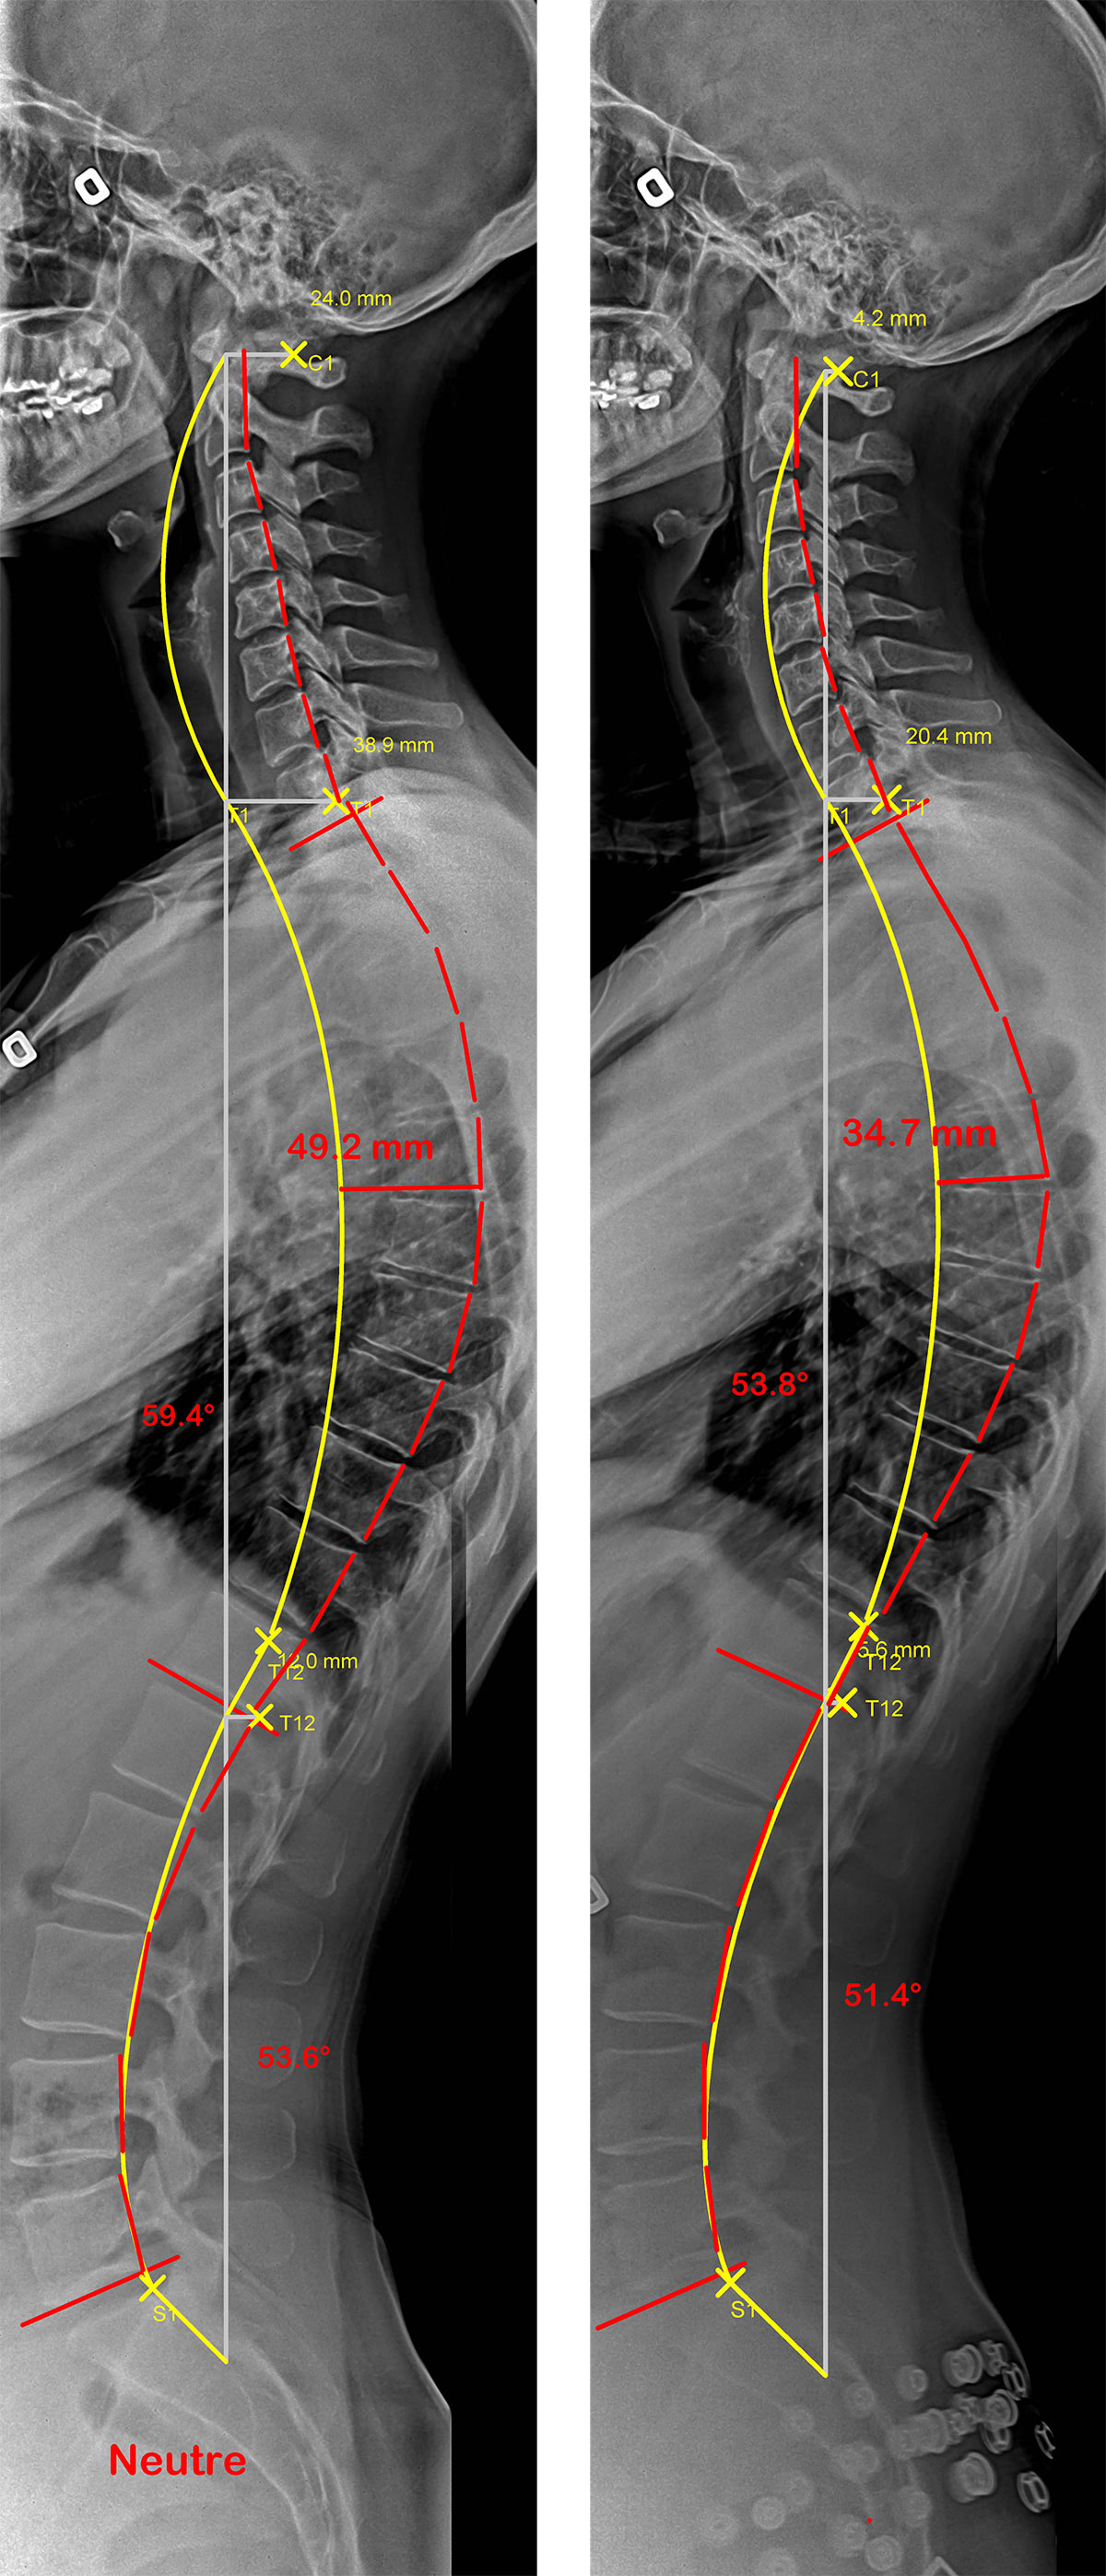

Le cas d’une adolescente avec une hypercyphose, sans et avec SpineCor®.

On remarque sur les radiographies que le simple fait de porter SpineCor® réduit la courbure de la colonne vertébrale d’environ 10° et améliore considérablement son alignement postural global car la ligne jaune représente l’idéal et la rouge le profil de la colonne vertébrale de la patiente.